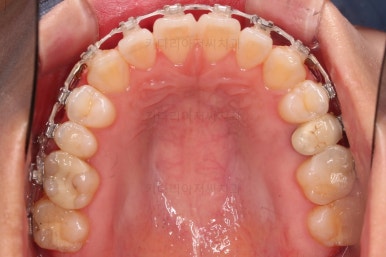

5. 치료의 종료

부산치아교정잘하는곳 키다리아저씨치과에서 치료를 종료했을 때의 사진입니다.

위아랫니가 가지런해졌고요.

다시 틀어지지 말라고 적절한 유지장치를 구성합니다.

보철 치아의 위치/크기로 인해 100% 중앙선은 맞기 힘드나 가장 잘 맞추어 놨고, 앞니의 각도도 매우 좋아졌습니다.